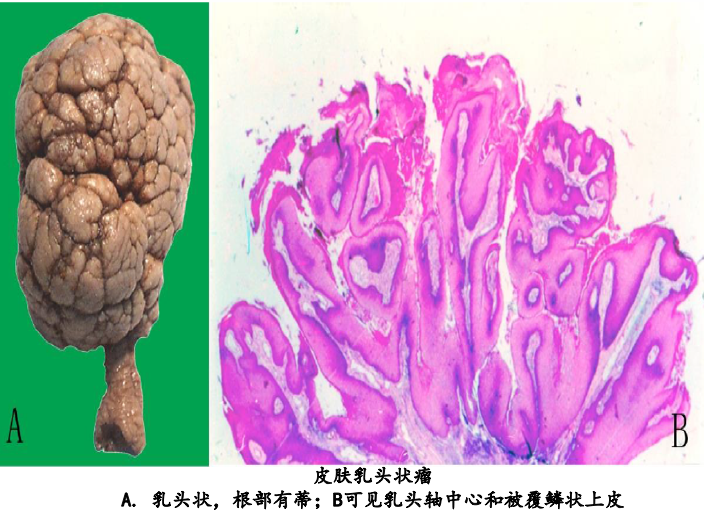

1.乳头状瘤(papilloma)

(1)大体:由复层的覆盖上皮,如鳞状上皮或移行上皮发生的良性肿瘤。肿瘤向表面呈外生性生长,形成许多手指样或乳头状突起,并可呈菜花状或绒毛状外观。肿瘤根部常有细蒂与正常组织相连。

(2)镜下:每一乳头表面覆盖增生的鳞状上皮或者移行上皮,乳头轴心由具有血管的分支状结缔组织间质构成。

鳞状上皮乳头状瘤临床常见于外阴、鼻腔、喉等处。其发生可能与人类乳头状瘤病毒的感染有关。外耳道、阴茎等处的鳞状上皮乳头状瘤较易发生恶变而形成鳞状细胞癌。移行上皮乳头状瘤可见于膀胱、输尿管和肾盂。膀胱的移行上皮乳头状瘤更容易恶变。